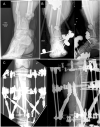

Bone devitalization is believed to be a critical determinant of complications such as infection or nonunion. However, intraoperative assessment of bone devitalization, particularly in open fractures and infections, remains highly subjective resulting in variation in treatment. Optical imaging tools, particularly dynamic contrast-enhanced fluorescence imaging, can provide real-time, intraoperative assessment of bone and soft tissue perfusion, which informs the tissues' ability to heal and fight infection. We describe a novel technique to apply indocyanine green-based fluorescence imaging, using a device that is frequently used in the operating room to assess skin or flap perfusion in plastic surgery, to assess bone and deep tissue perfusion in three pertinent cases: (1) a chronic infection/nonunion after a Gustilo type 3A tibia fracture (patient 1), (2) an acute Gustilo type 3C tibia open fracture with extensive degloving/soft tissue stripping (patient 2), and (3) an atrophic nonunion of the humerus (patient 3). In all three cases, fluorescence imaging (both time-specific fluorescence and maximum fluorescence) and derived kinetic maps of time-to-peak, ingress slope, and egress slope demonstrated clear spatial variation in perfusion that corresponded to the patient pathogenesis. The impact of this information on patient outcome will need to be evaluated in future clinical trials; however, these cases demonstrate in principle that optical imaging information has the potential to inform surgical practice, reduce the variation in treatment, and improve outcomes observed in these challenging patients.